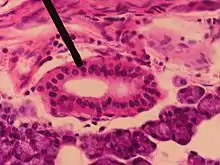

Comme d'autres canaux excréteurs, le canal parotidien est formé de trois couches : muqueuse, musculeuse et adventicielle. La couche muqueuse est initialement formée d'un épithélium à double couche, dans lequel s'insère des cellules caliciformes. Peu avant son ouverture dans la cavité buccale, l'épithélium se transforme en un épithélium stratifié. La couche musculeuse est formée de fibres musculaires lisses, disposées longitudinalement. Ces fibres musculaires vont permettre le péristaltisme du canal mais disparaissent progressivement en se rapprochant du muscle buccinateur, mais on retrouve des fibres musculaires issues de ce muscle qui vont s'étendre sur le canal [5]. La couche adventicielle est composée d'un tissu lipofibreux richement vascularisé [6].